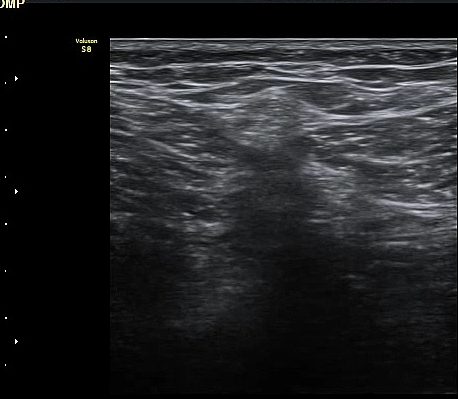

¹«¸­ ³»Ãø Á¾´Ü¸é°Ë»ç»ó ½ÉÇÑ °ñ±Ø°ú ¹Ý¿ù»ó¿¬°ñ Ç¥ÃþÀ¸·Î µ¹ÃâÀÌ °üÂûµÊ(»çÁø 1)

´ëÅð ³»Ãø, ¹«¸­ °üÀý¸é¿¡¼­ ¾à 10 cm ±ÙÀ§ºÎȾ´Ü¸é°Ë»ç¿¡¼­ ³»Ãø±¤±Ù°ú ºÀRHD±Ù(sartorius)

»çÀÌ¿¡¼­ º¹Àç½Å°æÀÌ °í¿¡ÄÚ Å¸¿øÇü ¾ç»óÀ¸·Î °í³ªÂûµÈ´Ù(»çÁø 2).

ŽÃËÀÚ¸¦ ¸»´ÜÀ¸·Î À̵¿ÇÏ´Ï º¹Àç½Å°æÀÌ ½½°³°ñÇϰ¡Áö¿Í  ºÀ°ø°¡Áö(sartorial branch)·Î

°¥¶óÁö´Â °ÍÀÌ °üÂûµÇ°í(»çÁø 3, 4, 5) µ¿¿µ»ó È­¸éÀ¸·Î º¸¸é ´õ¿í ¶Ñ·ÈÇÏ´Ù(÷ºÎ ÆÄÀÏ 1)

º¹Àç½Å°æ ½½°³°ñÇϰ¡Áö°¡ È®ÀÎµÈ »óÅ¿¡¼­ ´ëÅð ¾Õ¿¡¼­ ÃÊÀ½ÆÄÀ¯µµÇÏ ½½°³°ñÇϰ¡Áö

Â÷´ÜÀ» ½ÃÇàÇÏ¿´´Ù(÷ºÎ ÆÄÀÏ 2).